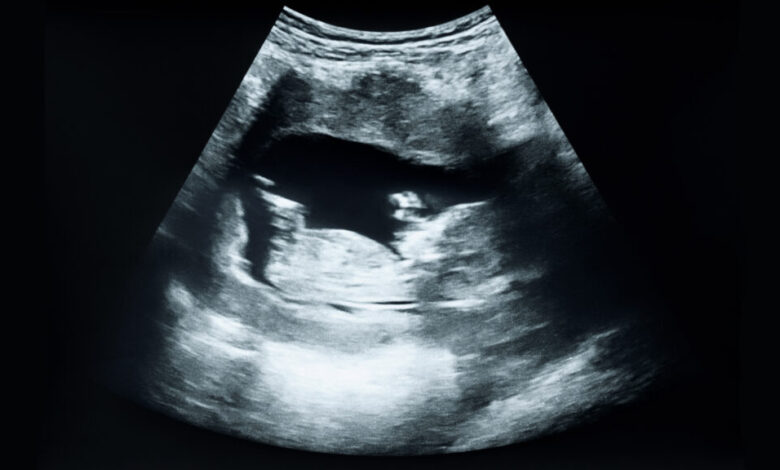

In another healthcare trend, the C-section rate in 2025 reached its highest level in a decade, according to new data from the CDC’s National Center for Health Statistics. The report reveals a rise in cesarean deliveries to 32.5% last year, with the rate for low-risk C-sections also climbing to 26.9%, the highest since 2012. Despite the increase in C-section rates, it’s important to note that higher rates do not necessarily equate to better birth outcomes.